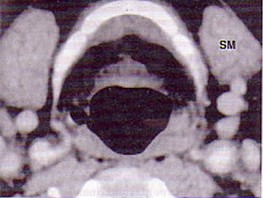

男,55歲,聲嘶6年,有長期吸煙史。檢查:無呼吸困難。喉鏡檢查:聲帶慢性充血,可見右側(cè)聲帶可見菜花樣新生物,右側(cè)聲帶活動(dòng)固定,喉部CT檢查如下圖: